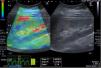

Stain wave elastography examinationPrior to elastography, all patients underwent a US examination to rule out perirenal hematomas. The strain wave elastography was done for all patients by the same radiologist within 3 days of renal biopsy. Ultrasonography, color Doppler ultrasonography (CDUS), and ultrasonography–elastography examinations were conducted using a Toshiba (Toshiba Medical Systems Corporation, Otawara, Japan) Aplio 500 ultrasound apparatus and a 3.5–5.0MHz convex probe. Following CDUS and greyscale B-mode, strain wave elastography; a software within ultrasonography machine was enabled. It is a semi-static and semi-quantitative approach. The tissue is compressed and decompressed by the operator. The contraction or expansion of the tissue in the direction of the compression is referred to as the “strain.” The lesion exhibited distortion and displacement as a result of the compression. Based on displacement, the software determines the lesion's elasticity score. Wave-like effects are produced by the compression and decompression stages. Using a free-hand method, 7–12 gentle repetitive compressions were made to create elastography images. Sinusoidal waves are the result of repeated compressions. The ultrasonography monitor shows the wave and the renal tissue. Three windows split apart on the monitor. Greyscale ultrasonography is shown in the first image, color-coded ultrasonography and elastography is shown in the second, and sinusoidal wave compression and decompression is shown in the bottom window. The various tissue stiffnesses are quantified and graphically depicted using a color scale. Firm areas are depicted in green with an intermediate consistency, soft portions in red, and hard areas in blue. The strain index (SI) serves as the technique's data unit that automatically calculated by the software and the measurement ought to be carried out during the decompression stage from the kidney's axial axis.13 To lessen the impact of anisotropy, the region of interest (ROI) was oriented so that its main axis ran as parallel to the main axis of the pyramids as feasible. Two ROIs were employed in the same depth. One was positioned on the renal sinus (reference ROI), and the other on the renal parenchyma. For statistical analysis, the mean of three measurements of the SI values from both the renal parenchyma and sinus were employed.14

Fig. 1 showing radiologist performing stain wave elastography examination

The statistical analysis of the elastography findings revealed that there were statistically significant differences between the studied groups regarding echogenicity, qualitative and semi quantitative (SI) elastography between studied groups (P value<0.001*, <0.001* & <0.001* respectively) (Table 2, Figs. 2–4).

A case of acute interstitial nephritis post chemotherapy with mild interstitial fibrosis (10%). The greyscale ultrasonography image showing mild increased parenchymal echogenicity with preserved cortico-medullary differentiation, the left one showing color-coded US – elastography image showing mainly green-red scale and the sinusoidal wave of compression and decompression seen in inferior aspect of image. The circles indicate the region of interests (ROIs). The upper ROI is on the parenchyma and the lower ROI is on renal fat sinus. The radial line on the sinusoidal wave indicates the end measurement (SI=0.74).

A case of light chain renal amyloidosis with moderate interstitial fibrosis (25%). The greyscale ultrasonography image showing moderate increased parenchymal echogenicity with preserved cortico-medullary differentiation, the left one showing color-coded US – elastography image showing mixed green-blue scale and the sinusoidal wave of compression and decompression seen in inferior aspect of image. The circles indicate the region of interests (ROIs). The upper ROI is on the parenchyma and the lower ROI is on renal fat sinus. The radial line on the sinusoidal wave indicates the end measurement (SI=2.74).

A case of focal necrotizing GN with small vessel vasculitis with marked interstitial fibrosis (55%). The greyscale ultrasonography image showing marked increased parenchymal echogenicity with relatively poor cortico-medullary differentiation, the left one showing color-coded US – elastography image showing mainly blue-green scale and the sinusoidal wave of compression and decompression seen in inferior aspect of image. The circles indicate the region of interests (ROIs). The upper ROI is on the parenchyma and the lower ROI is on renal fat sinus. The radial line on the sinusoidal wave indicates the end measurement (SI=3.17).